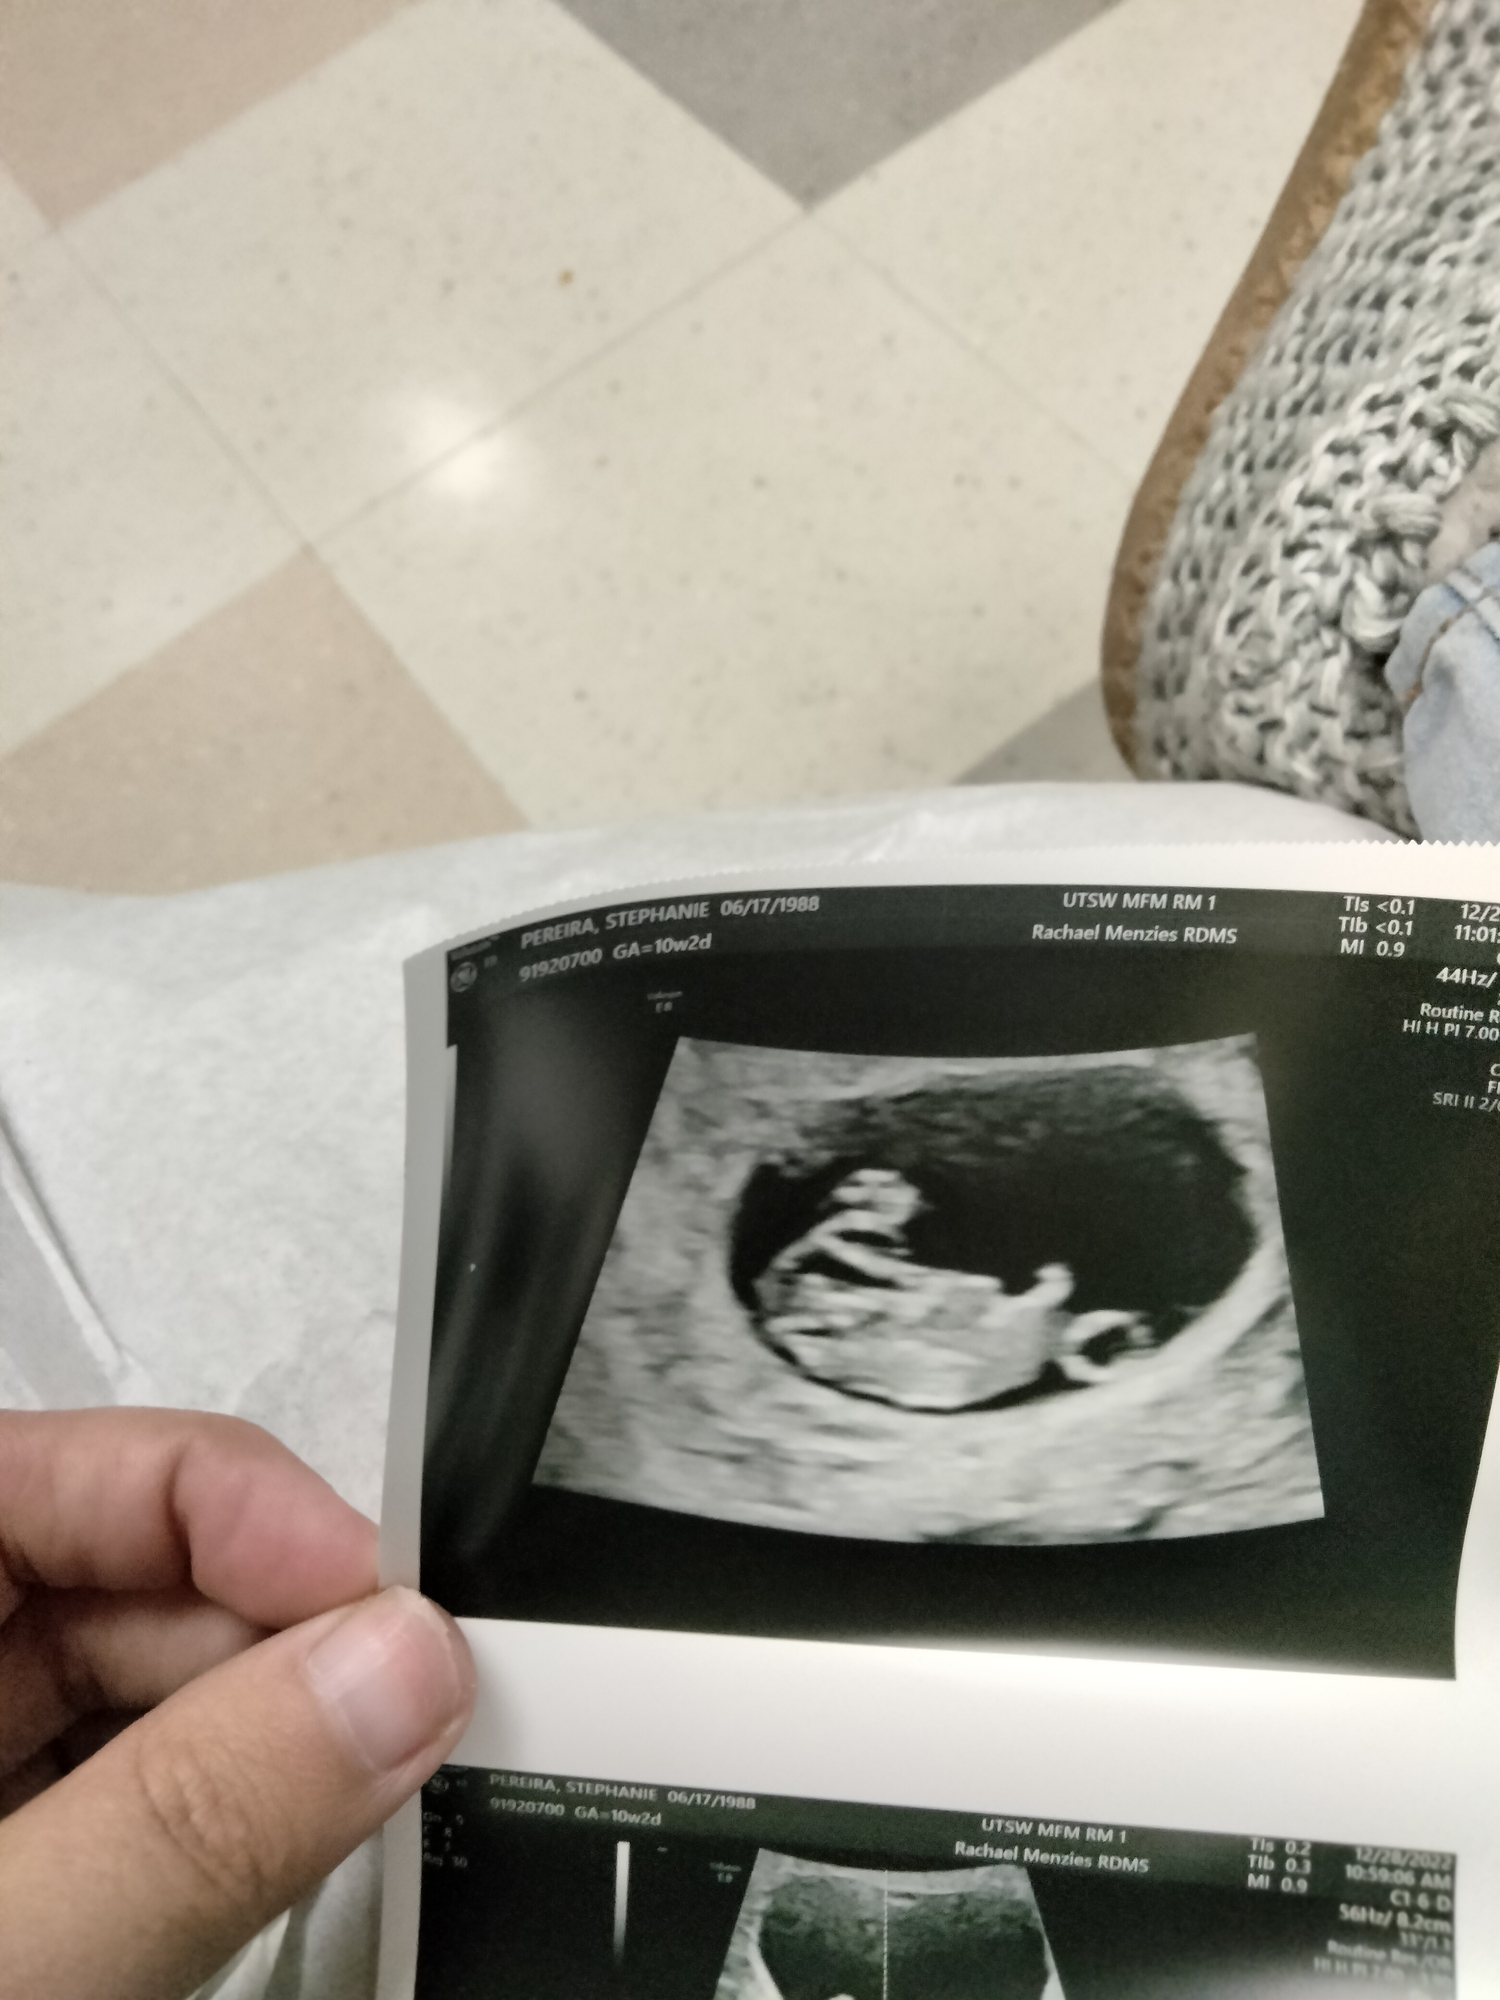

Finally got my ultrasound today! My EDD changed from 8/6 to 8/1 (but I love the crew in the august discussions board, it tried to get me to the July board but I’m sticking here)

Baby is 10w6d today! I’m a week ahead and a week closer from getting away from this damn morning sickness!!

Little peanut’s heartbeat is 165. I edited the photo to describe it. Look at that chunky belly!! And yes I cried too! My partner looked like a deer in headlights happy.